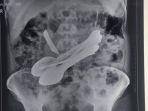

Dokter Terkejut: Dalam Perut Pria Ini Ditemukan Sendok, Pisau dan Obeng

Kejadian unik dan aneh terjadi di India. Dokter yang ada di sebuah rumah sakit di negara itu dilaporkan sangat terkejut